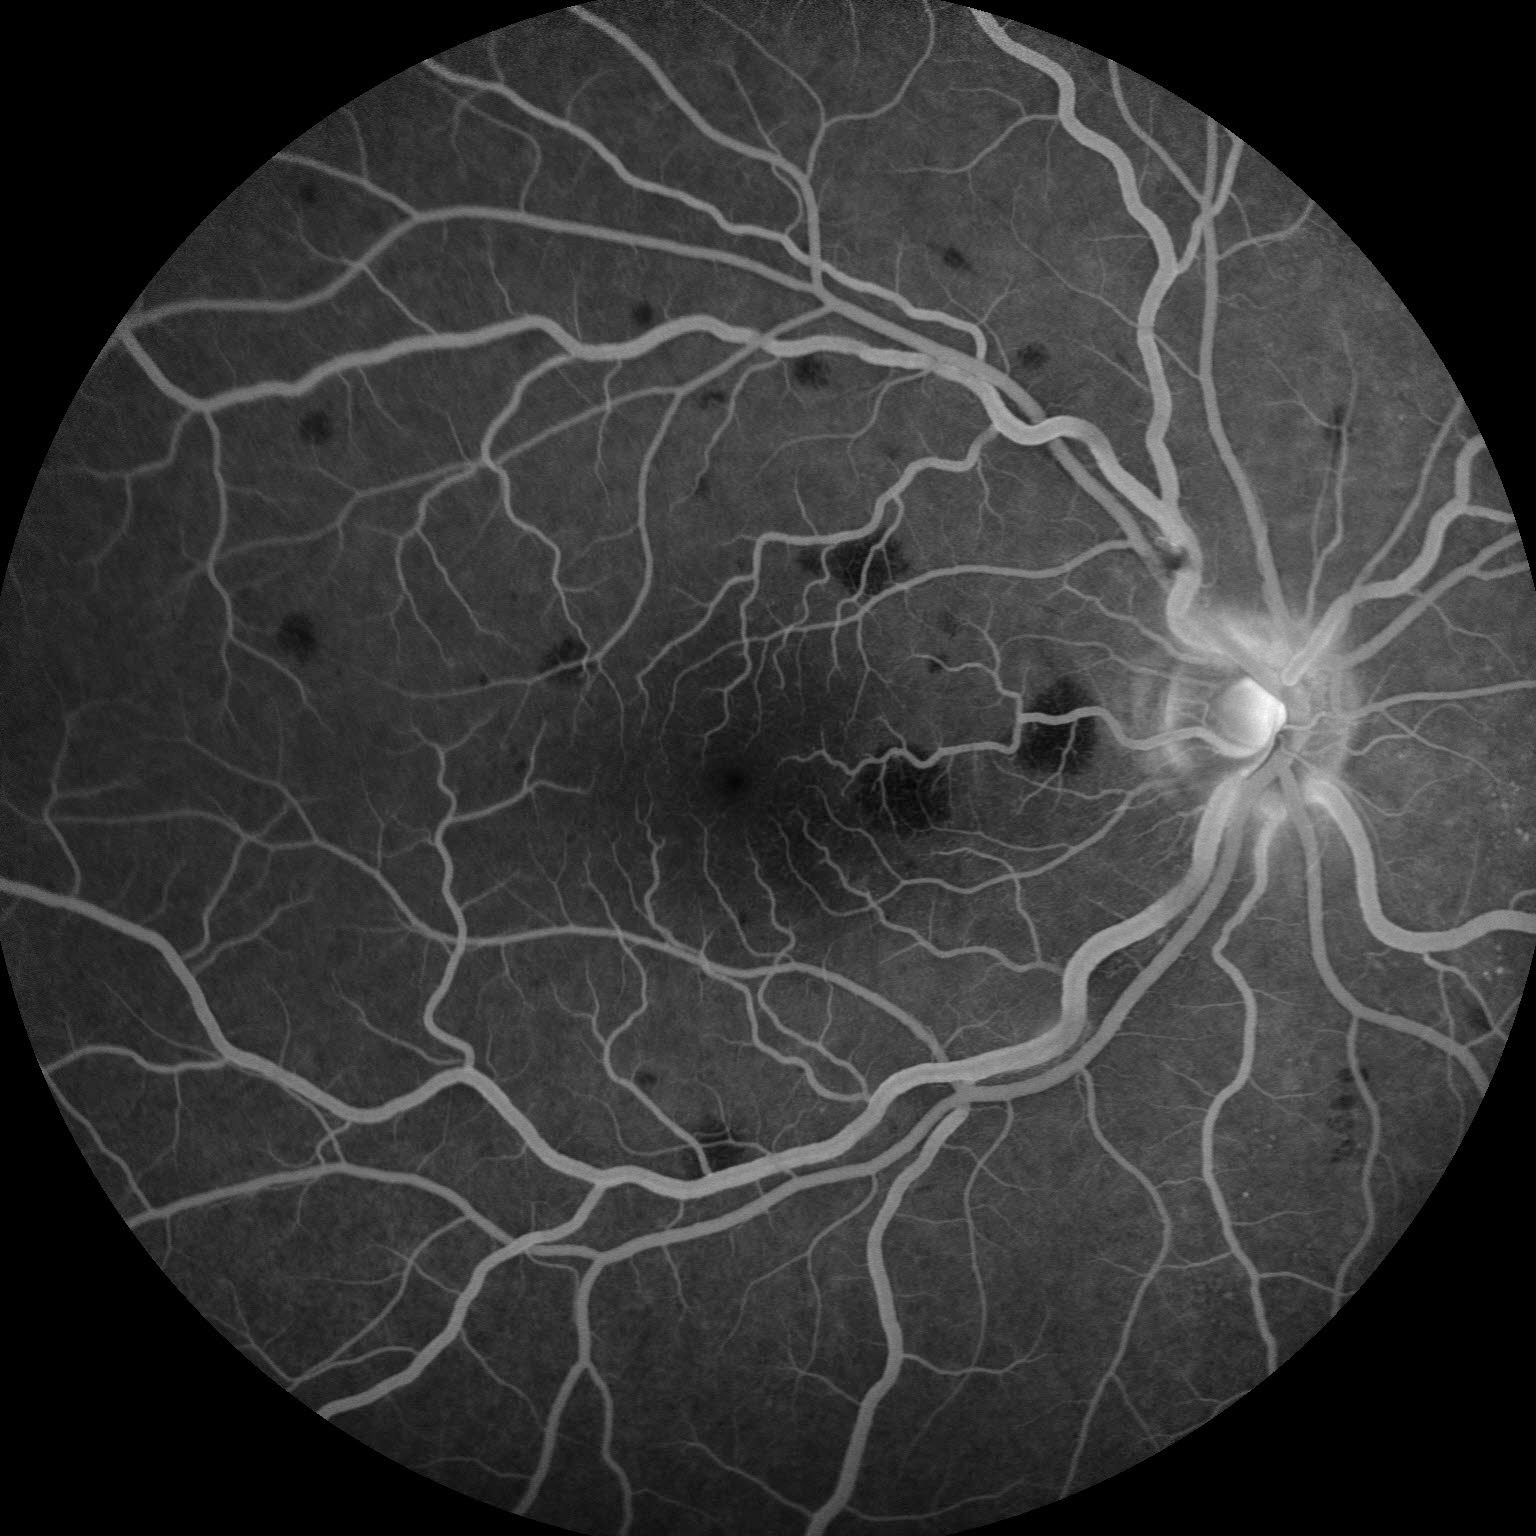

PAMM Presented by Karla Woods, OCT-C This photograph received Second Place, Fluorescein Angiography (30° - 40°)in the 2025 OPS Scientific Exhibit. Filed Under Cornea OPS Photo